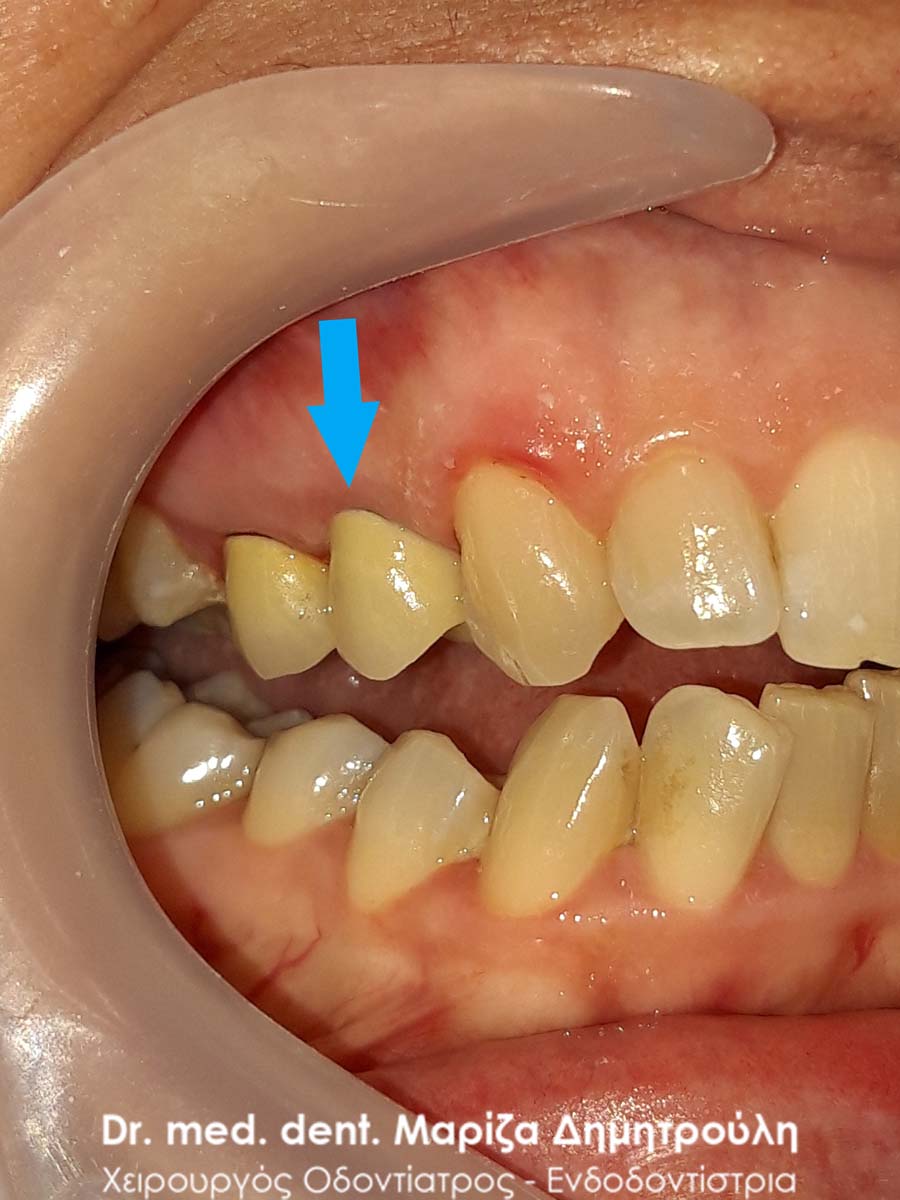

Περιστατικό – Ολοκεραμική στεφάνη / θήκη ζιρκονίου στον άνω αριστερό γομφίο

Η ασθενής επισκέφτηκε το ιατρείο μας γιατί πονούσε στον πρώτο άνω αριστερό γομφίο. Η κλινική και ακτινογραφική εξέταση φανέρωσε την αναγκαιότητα απονεύρωσης του δοντιού. Μετά το πέρας της ενδοδοντικής θεραπείας και εφόσον το οδοντικό έλλειμα ήταν μεγάλο, κρίθηκε απαραίτητη η προστασία του απονευρωμένου δοντιού με ολοκεραμική θήκη.

Αρχική κλινική εικόνα του δοντιού με το προσωρινό σφράγισμα απονεύρωσης